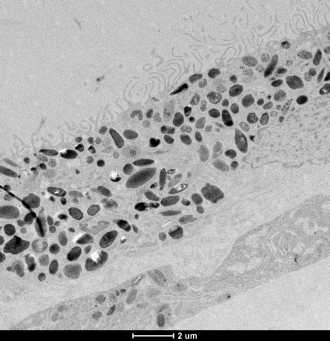

Fluorescent imaging of retinal pigment epithelium. Credit: Dr Grace Lidgerwood

Retinal pigment epithelium cells line the back of the retina and are essential to the health and functioning of the retina. Their degeneration is associated with the death of photoreceptors, which are light-sensing neurons in the retina that transmit visual signals to the brain and are responsible for the loss of vision in AMD.

Retinal pigment epithelium cells